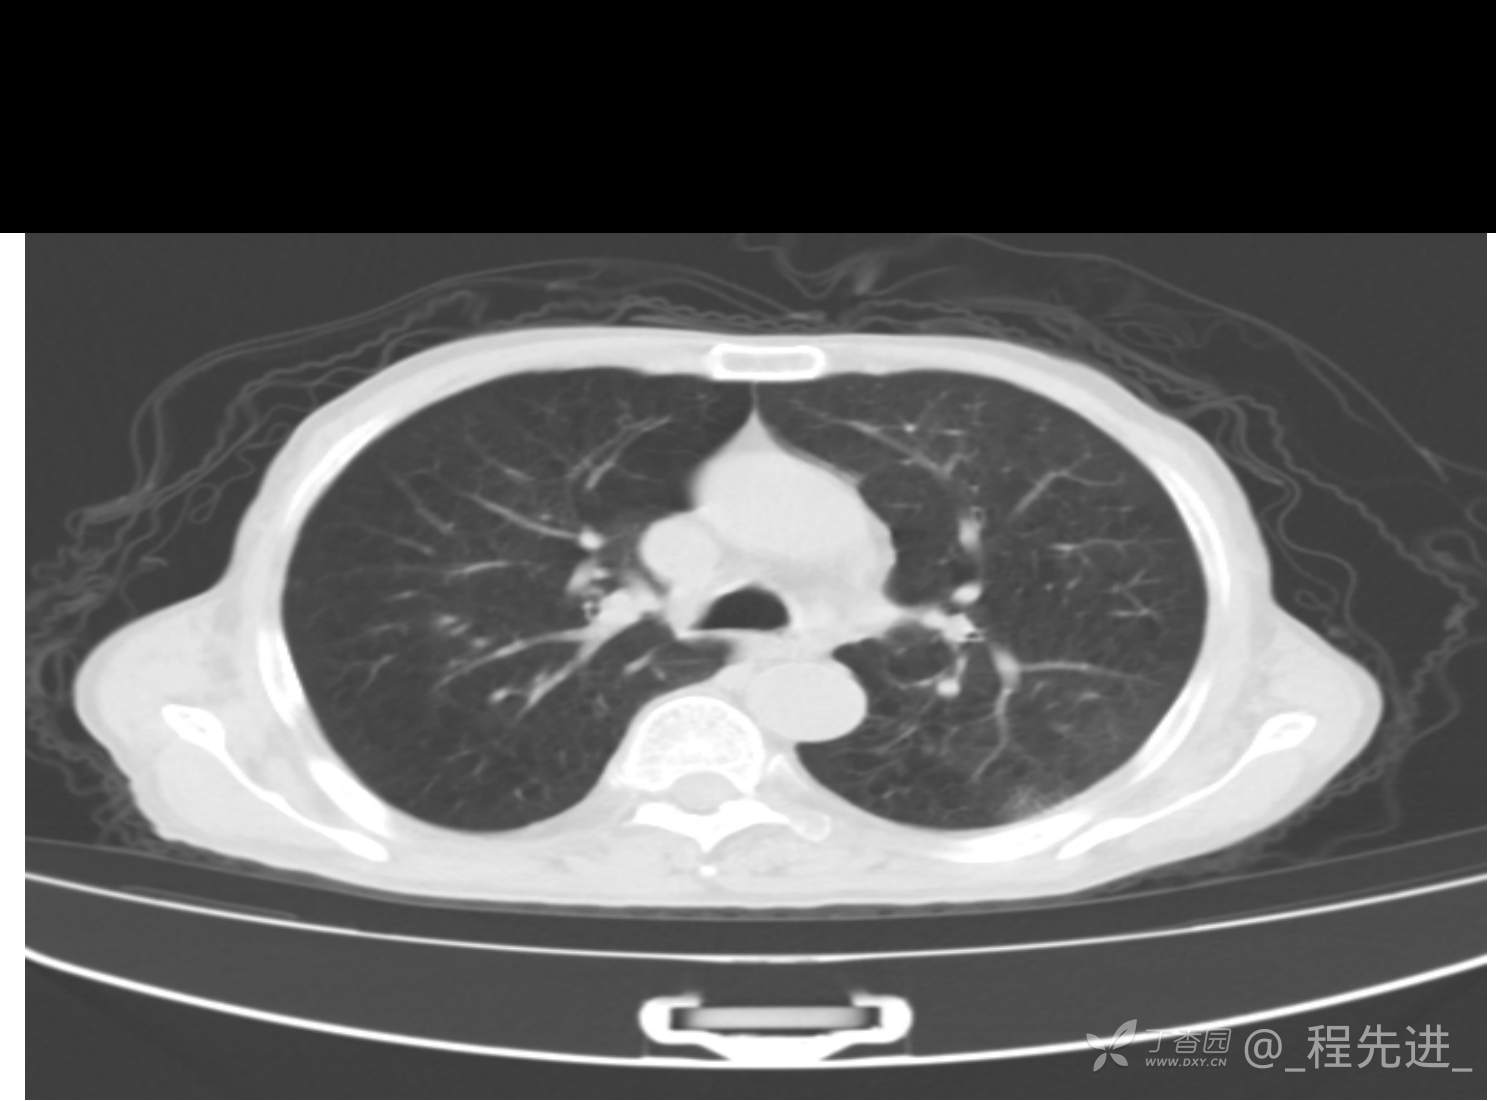

患者性别:男

患者年龄:81岁

简要病史:反复咳嗽、咳痰20余年,加重1周。两肺呼吸音低,可闻及散在干湿啰音。